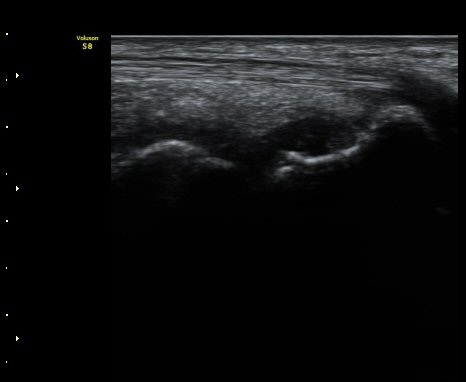

ÃÊÀ½ÆÄ °Ë»ç

¼Õ¸ñÀÇ Á¾´Ü

ÁÖ»ó°ñ ¼±»ó°ñÀýÀº ´Ü¼ø¹æ»ç¼± ÃÔ¿µ ½Ã È®ÀεÇÁö ¾ÊÀº °æ¿ì°¡ ¸¹Àºµ¥ ÀÌ ¶§ ÃÊÀ½ÆÄ

°Ë»ç°¡ ÁÖ»ó°ñ °ñÀý Áø´Ü¿¡ ¸Å¿ì À¯¿ëÇÏ´Ù. ±×·¯¹Ç·Î ¼Õ¸ñ ´ÙÄ£ ÈÄ Áö¼ÓÀûÀÎ ÅëÁõÀ»

È£¼ÒÇϰí ÁÖ»ó°ñ ºÎÀ§ ¾ÐÅëÀ» º¸ÀÌ´Â °æ¿ì ÃÊÀ½ÆÄ°Ë»ç¸¦ ½ÃÇàÇÏ¿© ÁÖ»ó°ñ °ñÀý ¿©ºÎ¸¦

È®ÀÎÇØ¾ß ÇÑ´Ù.

ÃÊÀ½ÆÄ°Ë»ç¸¦ ½ÃÇàÇÒ ¼ö ¾ø´Â °æ¿ì´Â ÄÄÇ»ÅÍ ÃÔ¿µ°Ë»ç¸¦ ÁÖ»ó°ñ °ñÀýÀ» È®ÁøÇÒ ¼ö ÀÖ´Ù.